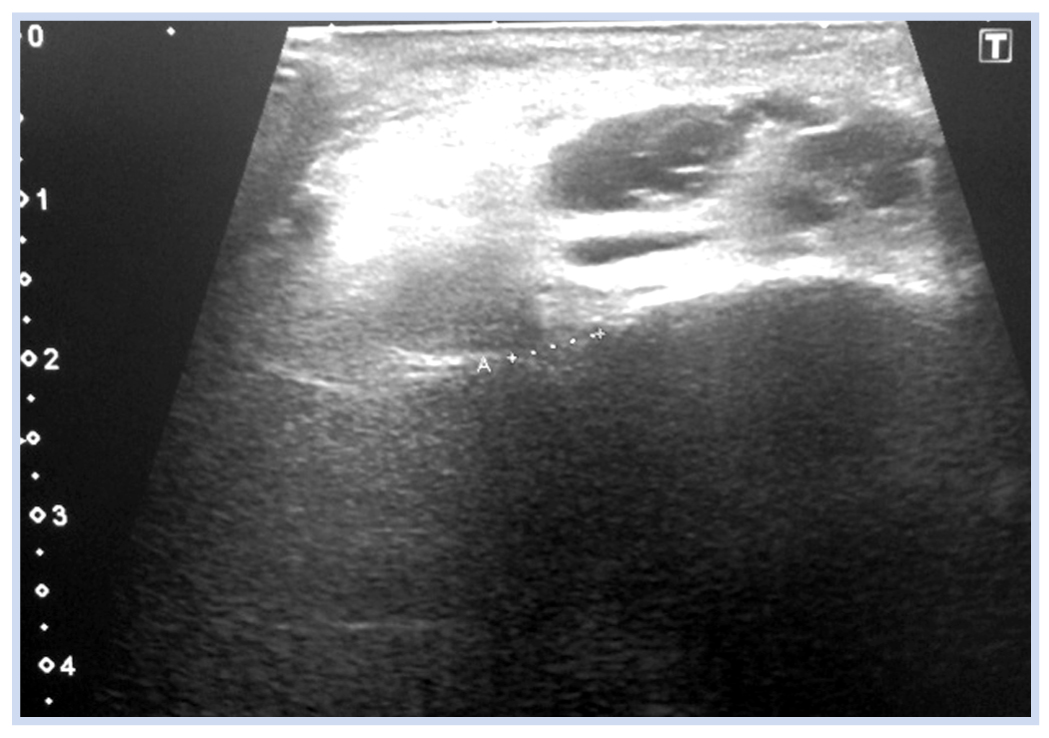

Мальчик, 16 лет, диагноз «Закрытый перелом обеих лодыжек правого голеностопного сустава с подвывихом стопы кнаружи. Супинационно-эверсионный механизм травмы». Травма получена в результате падения на льду. По данным ультразвуковой диагностики был диагностирован частичный разрыв передней порции дистального межберцового синдесмоза. Выполнен остеосинтез внутренней лодыжки спицами, дистальный межберцовый синдесмоз фиксирован синдесмозной системой (Arthrex Tightrope Ankle), перелом латеральной лодыжки фиксирован 1/3 трубчатой пластиной. Внешняя иммобилизация осуществлена гипсовой лонгетой. Контрольная рентгенография и исследование микроциркуляции в области перелома методом лазерной допплеровской флоуметрии выполнены через 8 нед. после операции. На рентгенограммах имеются признаки зажившего перелома, по данным флоуметрии наблюдается активация капилляризации тканей и нутритивного кровотока в условиях регенераторного процесса. Спицы удалены через 8 нед., конфигурация сустава восстановлена полностью (рис. 10–13).

Данные лазерной флоуметрии по красному и инфракрасному каналу, согласно критерию Шапиро– Уилка, имели положительный показатель нормальности распределения. В результате расчета нормальных и относительных показателей вариации получено, что данные совокупности однородны с малой вариацией, что говорит о правильности выбора сроков исследования и подтверждает рентгенологические данные.

Метод лазерной допплеровской флоуметрии с вейвлет-спектром колебаний кровотока (рис. 14) и оценкой миогенного компонента осцилляций позволил укрепить доказательную базу рентгенологических признаков заживления перелома согласно установленным срокам консолидации.

Рис. 14. Вейвлет-спектр колебаний кровотока: по горизонтали — частота (F) осцилляций (в Гц), по вертикали — амплитуда (А) колебаний (в п.е.).